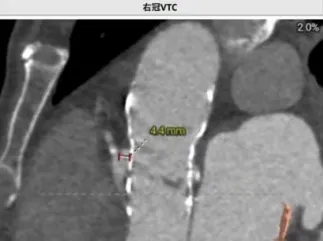

术前讨论:患者77岁老年男性,3年前行TAVR术,此次再发主动脉瓣关闭不全,经评估排除感染,考虑主动脉瓣生物瓣毁损,患者心衰重,消瘦、虚弱,经多学科讨论,TAVR in TAVR手术指征明确,考虑行TAVR in TAVR治疗,术前评估瓣架内径:瓣环26.6,LVOT 26.6,瓣架位于瓣环以下:5(无窦)-13(左窦)mm,左侧冠脉高度12.1,右侧13.4,左冠VTC5.3mm VT-STJ:0mm,右冠VTC4.4mm VT-STJ0mm, 主动脉弓部角度可,存在钙化,双侧髂股动脉内径可,右侧股动脉分叉位于股骨头平面中部 左侧股动脉分叉位于股骨头下缘中部,建议左侧入路,拟植入29号瓣膜,因患者冠脉风险大,需控制瓣膜植入深度,拟控制S3上缘位于启明第3-4个交接点处,同时需关注冠脉(Guidzilla预置保护)。

(1)TAVR in TAVR中需重点评估冠脉风险,相较于自体瓣膜评估,瓣中瓣植入过程中,需重点关注几个指标(图6):coronary risk plane(CRP),New-skirt Plane(NSP),VTA:VTC,VTAoS,VTSTJ。主要原因在于人工瓣膜将会形成新的封堵平面,术前评估中需重点关注。